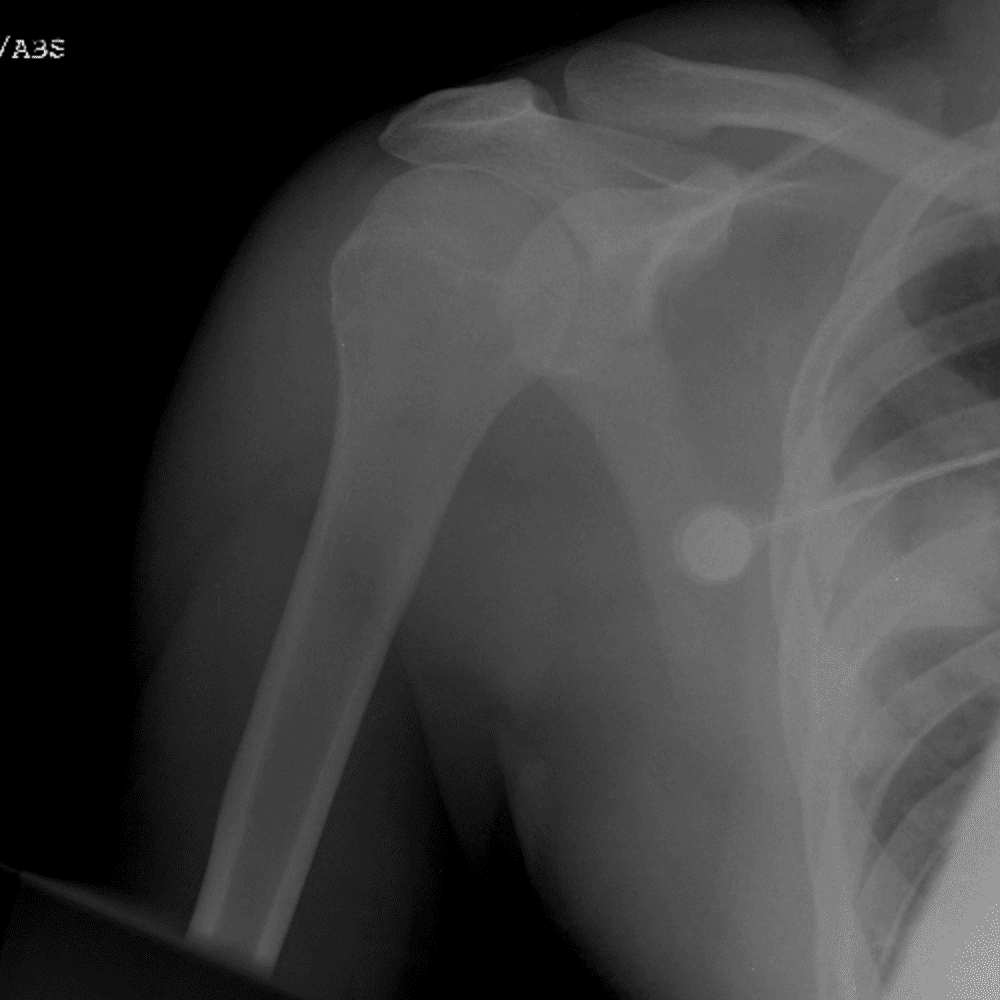

Simuliert den Dienst durch subtile oder schwierige Fälle und einige Normalbefunde.

30 Fälle